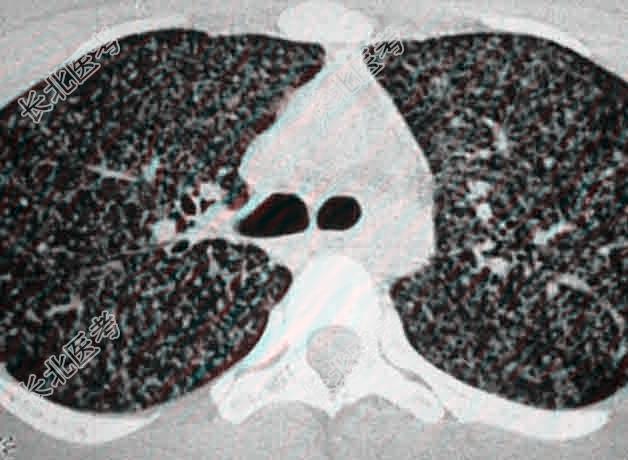

- [材料题] 一名患有糖尿病的68岁妇女,因发烧.咳嗽.咯痰.气促20天而来诊。胸片示两肺散在性栗粒状.等大.均匀的病灶。痰检结核菌阴性,1:2000的OT(5TU)试验阴性,经一个月康结核药物强化治疗复查,病灶吸收好转。

- 多项选择题1.提示:胸部CT如图。